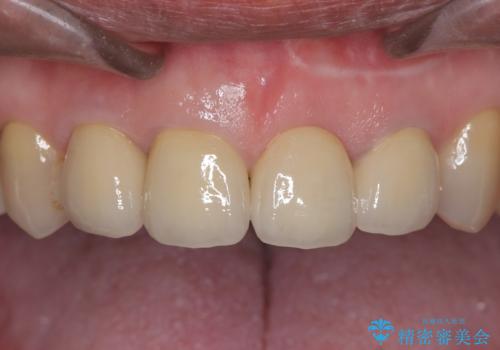

左上1は抜歯と同時にインプラントを埋入し、骨や歯ぐきの形態を維持しながら治療を進めました。左上2は歯根端切除術により感染部位を除去し、保存治療を実施。右上1・2も含めた前歯4本をセラミッククラウンで修復し、自然な色調と形態を再現しました。治療後は、噛み合わせの安定とともに、美しく自然な前歯を回復することができました。患者様からも「見た目がとても自然で、自信を持って笑えるようになった」と喜びの声をいただきました。